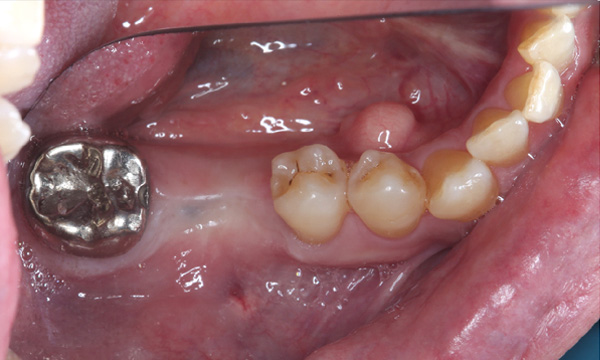

| 年代・性別 | 50代 男性 |

|---|---|

| 主訴 | 右下の歯がないのでインプラントをして欲しい |

| 治療期間 | 約6ヶ月 |

| 費用 | 600,000円 |

| 治療内容 | インプラント、骨造成、結合組織移植、セラミック修復 |

| 治療に伴うリスク | インプラント周囲炎 セラミックの破折、脱離 |

*キャンセルポリシーをご一読のうえご予約ください